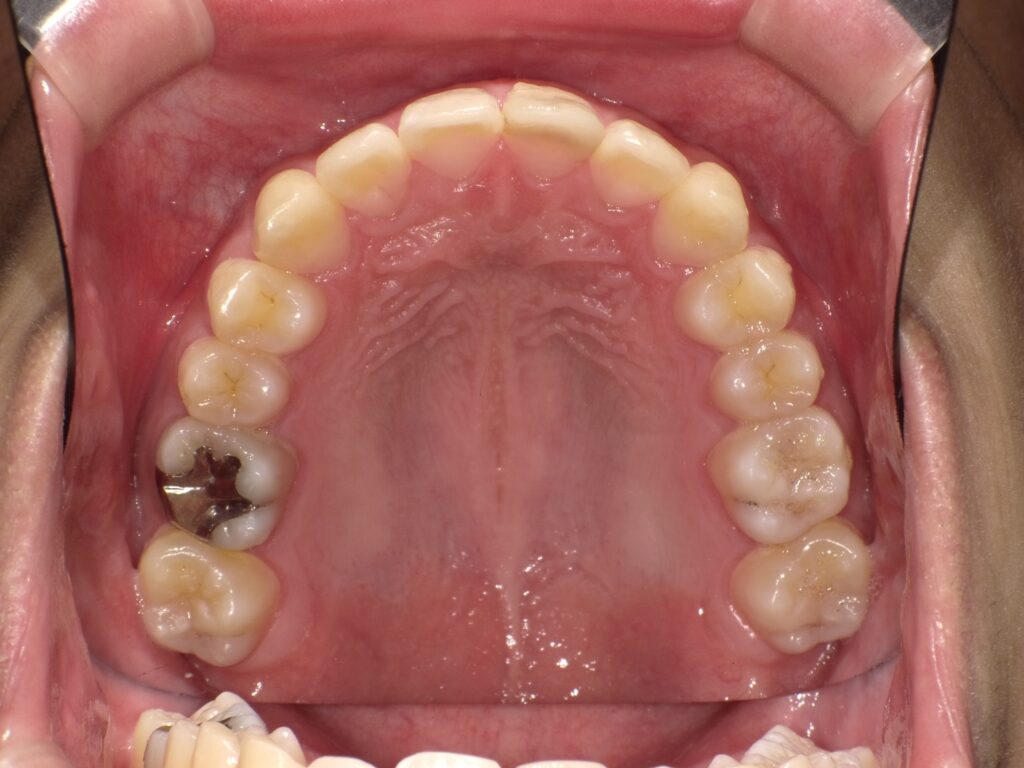

• 【治療後】

隙間がきれいに閉じ、自然な歯並びになっているのが分かります。